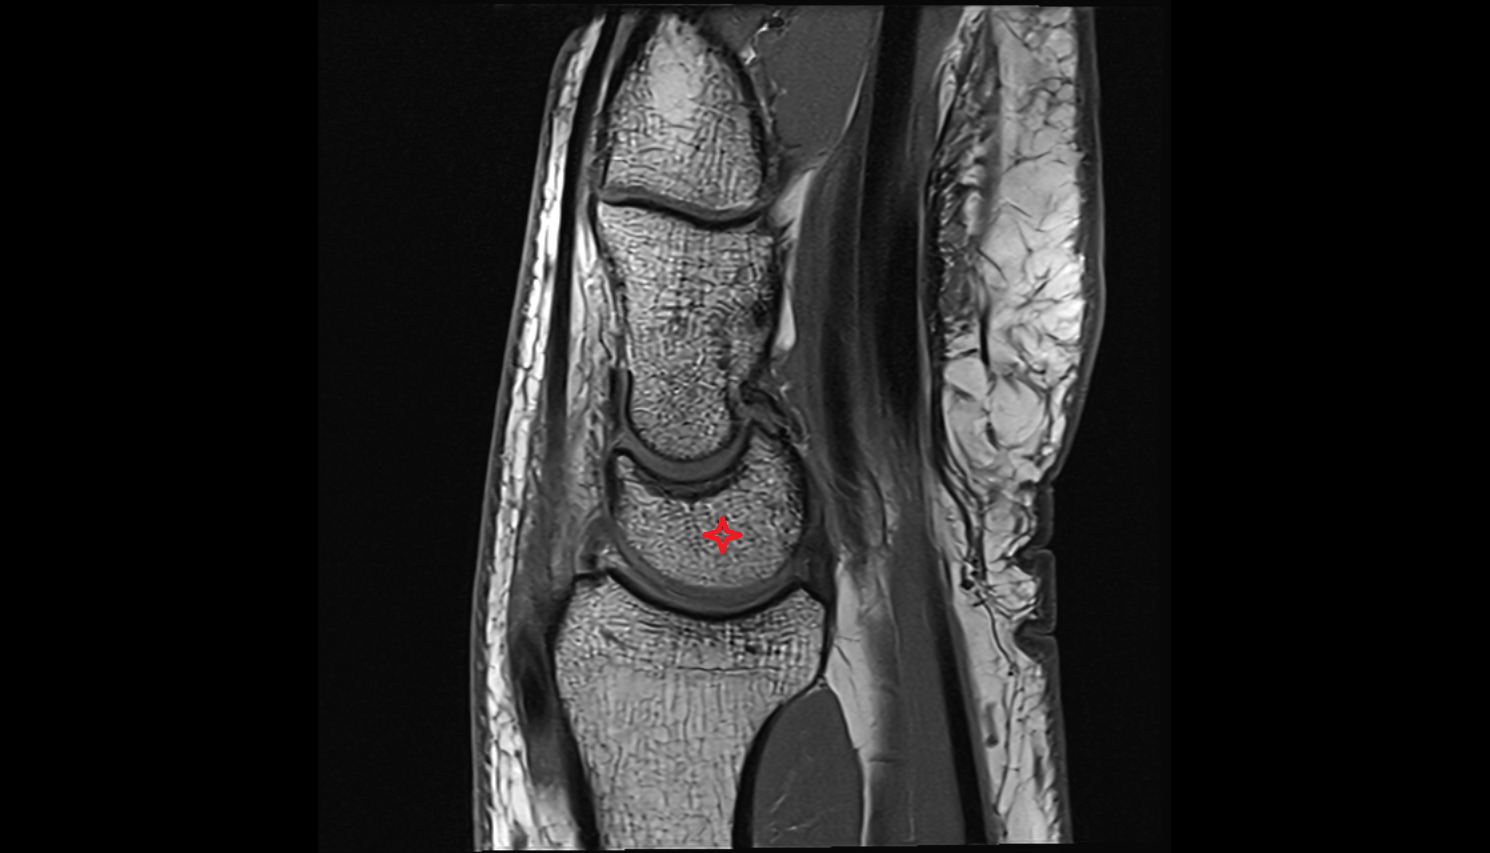

- Fetal elbow